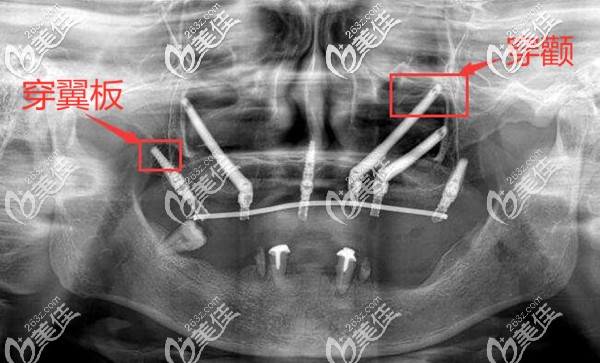

简单的来说,穿颧穿翼板种植牙技术,是专门解决上半口牙齿缺失牙槽骨又萎缩比较重的种牙问题;也是一种高难度种植牙技术。

穿颧穿翼板种植,主要是用比传统种植体多出3-4倍长度的种植体,植入到颧骨和翼板骨部位。

穿颧穿翼板种植牙可谓是种植界顶峰的技术,对医生的技术要求非常高;所以种植前医生通过各种检查,详细了解种植区域邻近的动脉、静脉和神经的位置,只有这样才能够避免手术的风险,以及术后的并发症,如出血、损伤面部和眼部神经等。

不过,也不用过于担心,因为现在能做穿颧穿翼板种植的医院,都会现在3D打印来出来的颌骨模型模拟手术,真正的手术中还配备有3D导板,手术中的定位也会更精准。